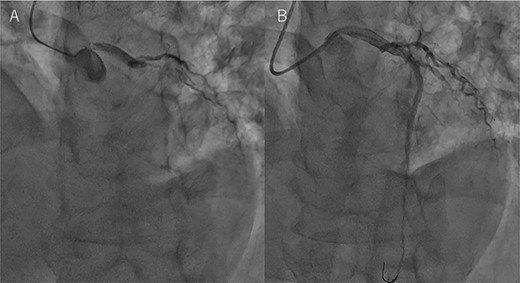

An Asian male in his 60s complained of sudden chest pain and was referred to a regional hospital. Electrocardiography showed massive ST-elevation in V1-4, and emergency coronary angiography revealed occlusion of the left anterior descending (LAD) artery (Fig. 1a). PCI was successfully performed (Fig. 1b), and IABP was inserted. Maximum value of creatine-kinase was 10 080 U/l, and his left ventricular function was severely impaired with an ejection fraction of 30%. High dosage of catecholamine was administrated and his hemodynamic status gradually recovered; however, he fell into profound cardiogenic shock on post PCI Day 6. Chest X-ray showed significant cardiomegaly (Fig. 2a), and trans-thoracic echocardiography revealed cardiac tamponade.

Coronary angiography findings. (A) Pre PCI, the LAD artery was completely occluded. (B) Post PCI, the LAD was recanalized.

Chest X-ray findings. (A) Preoperative, (B) immediately after operation and (C) just after explantation of Impella.

The patient was transferred to our hospital where emergency operation was performed via median sternotomy. Oozing type LVFWR on the anterior wall was found, and was treated with a non-suture technique using TachoSil (Nycomed, Zurich, Switzerland), and without cardiopulmonary bypass. Thereafter, the IABP was removed and Impella CP was inserted percutaneously from the right groin (Fig. 2b). His hemodynamic condition recovered dramatically, and the Impella was removed on postoperative Day 5 (Fig. 2c). The patient was discharged home on postoperative Day 18, and 3 months after the onset of MI, he is doing well.